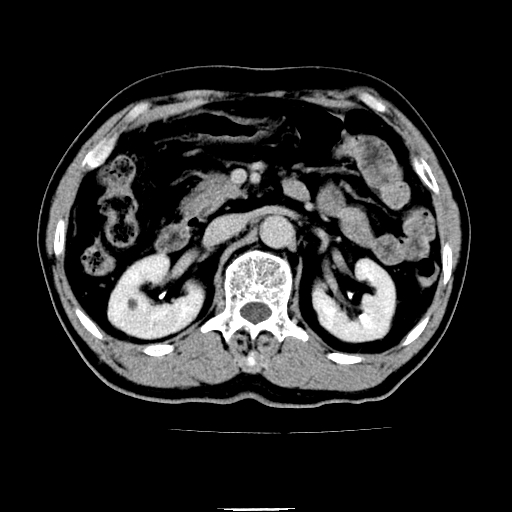

以下是引用chenqiong在2010-3-25 20:56:00的发言:[br]1、胆囊炎,胆囊息肉[br]2、肝内胆管及胆总管扩张,胆总管下端结石[br]3、十二指肠乳头旁憩室

以下是引用zxl51642在2010-3-26 10:47:00的发言:[br]胆囊炎,胆囊息肉,胆总管扩张,但未看到明显肿块,肝内胆管扩张不像恶性,炎性狭窄或阴性结石可能吧,建议mrcp,右肾小囊肿